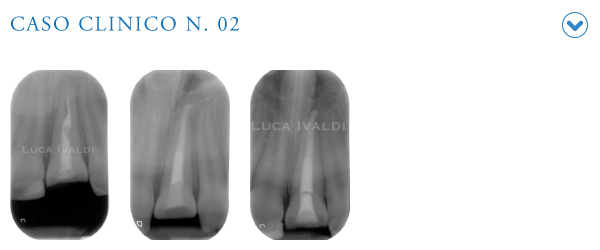

Dott. Luca Ivaldi

Master Endodonzia - Dental School - Lingotto